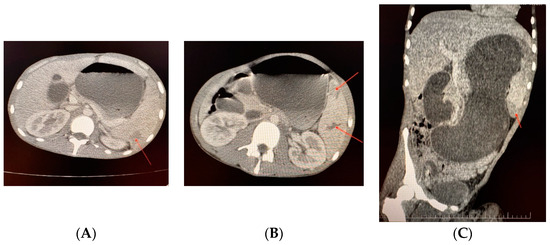

Case 3. A 19-year-old patient with severe haemophilia B, treated on-demand, was admitted to the clinic due to severe abdominal pain after trauma. The pain was located in the left hypochondrium, mesogastrium, and epigastrium. Upon clinical examination, the patient was found to have massive abdominal distention associated with a large hematoma on the left elbow and calf and debilitating arthropathy of both knees. An abdominal and pelvis computed tomography (CT) scan showed gastric dilatation, an enlarged spleen, and two splenic hematomas located at the mid-body and inferior pole. (Figure 3A–C). The patient’s haemoglobin levels dropped to 3 g/dL, and with the family’s consent (belonging to the Jehovah’s Witnesses), the patient received four units of packed red blood cells (pRBCs). The intervention was performed after draining 2.5 L of bloody stomach fluid, administering coagulation factor IX product, and ligating the splenic artery and vein: splenectomy was conducted, and a 1.5 kg large spleen was removed, revealing a small rupture in the middle of the spleen’s capsule. The patient initially recovered well after the surgery. However, on the third-day post-operation, minor bleeding was observed at the lower part of the surgical incision, along with a hematoma on the left calf and cutaneous necrosis on the left elbow hematoma. Consequently, a simultaneous surgical intervention was decided upon, which included draining the minimal supra-aponeurotic hematoma located inferior to the surgical incision and evacuating a large (0.4 L) hematoma in the left calf, along with excising the necrotic skin lesion (6/4 cm) on the left elbow and partially covering it with skin taken from the left thigh. The patient’s recovery was successful under the standard treatment regimen with FIX concentrate, and he was discharged after 27 days. The total cost for hospitalisation, medication and consumables was EUR 32,763.70 (92.80% for plasma-derived FIX concentrate). In all cases we respected the dosages for substitution as recommended in surgical interventions (Table 3); in the period of reha-bilitation, in order to prevent traumatic bleedings connected to the physical activity, we aimed at least 10–15 UI/dl of coagulation factor level.

Figure 3.

(A–C) Case 3—Abdomen and pelvis computed tomography scan with contrast (anteroposteriorly and sagittal view). Hepatosplenomegaly. Right liver lobe of 20 cm, left liver lobe at the axillary line. The kidneys and pancreas were normal. Gastric dilatation. Spleen enlarged 15/6/19 cm, with mid-body capsular fissure, two hypo-capturing areas at the inferior pole (9/2/3 cm) and posterior median region (3/3 cm), and subcapsular hematoma. Without abdominal-pelvic collections.